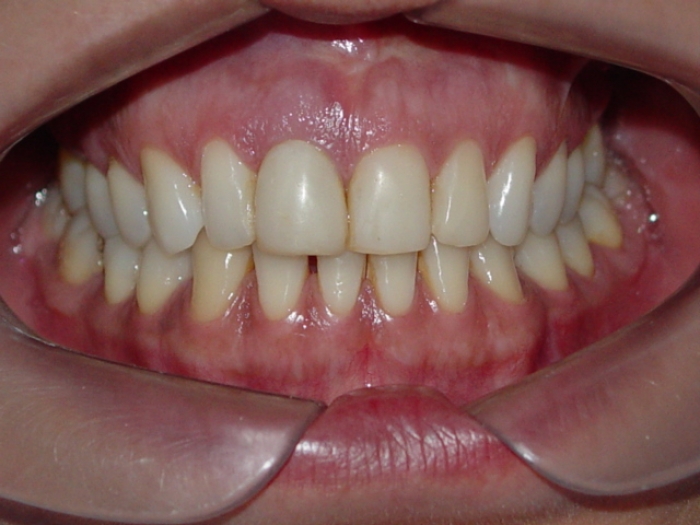

Sorriso após prótese provisória instalada